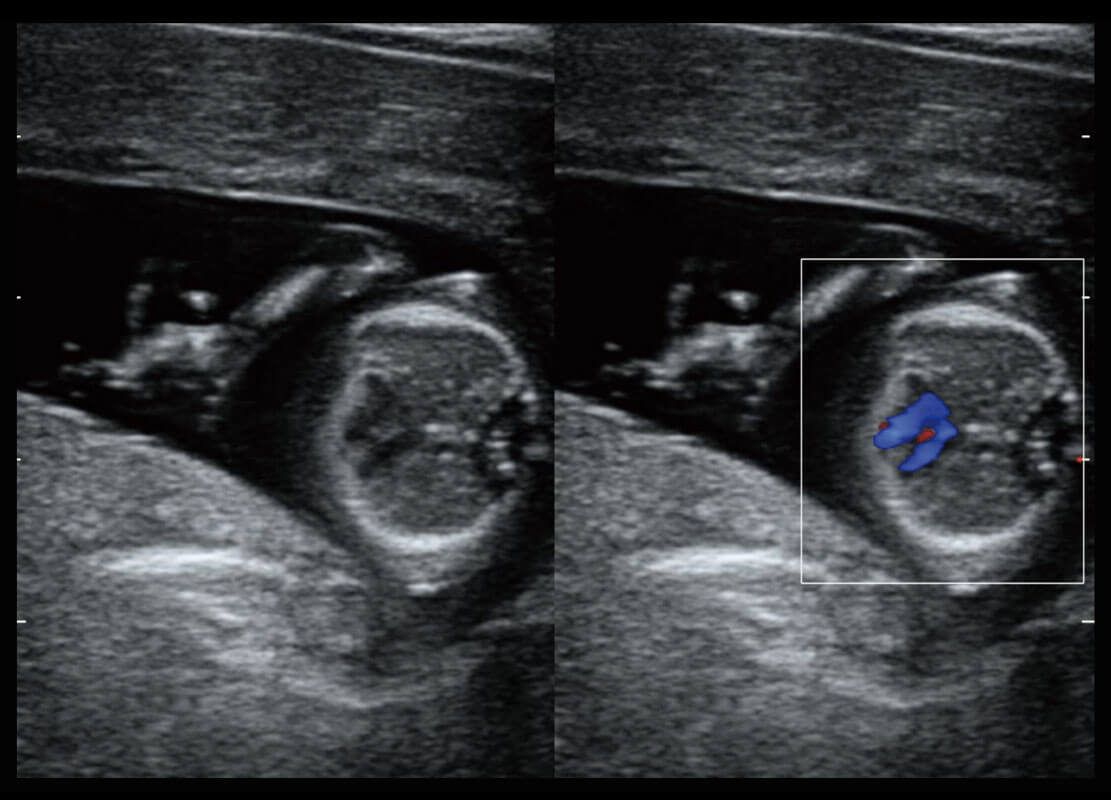

四腔切面

四腔心血流